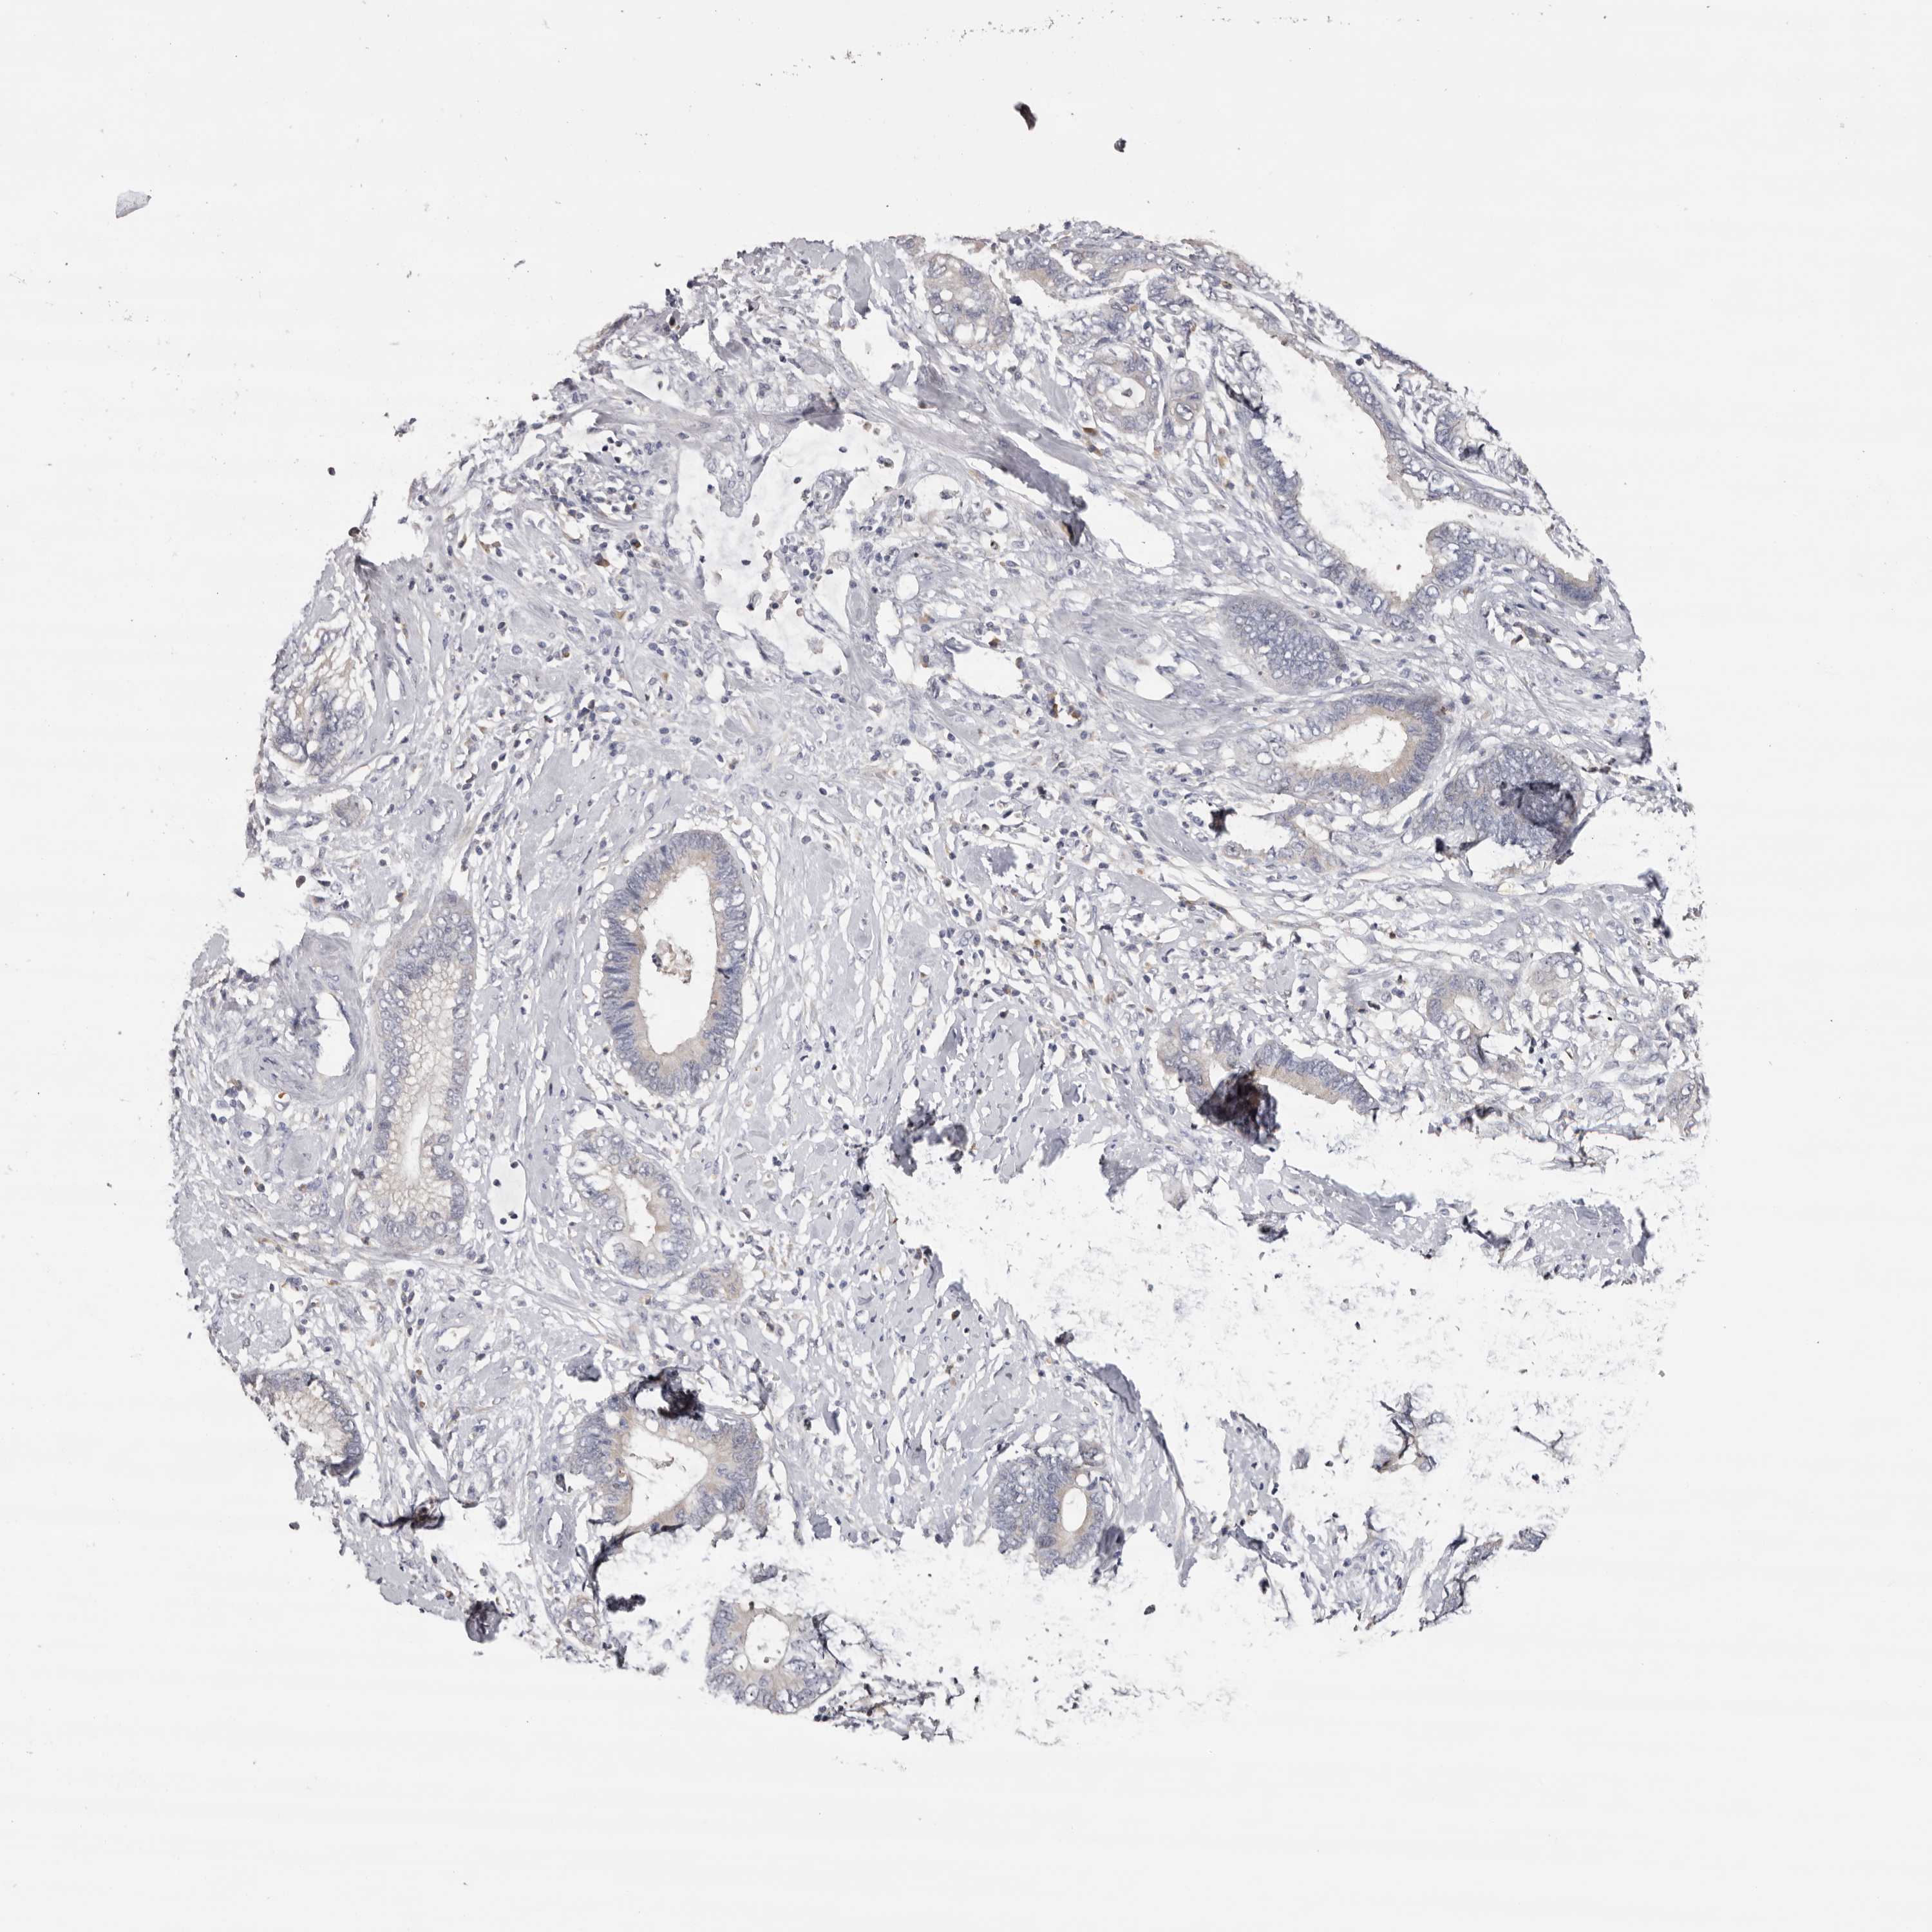

CERVICAL CANCER - Protein expressioni

A mouse-over function shows sample information and annotation data. Click on an image to view it in a full screen mode. Samples can be filtered based on level of antibody staining by selecting one or several of the following categories: high, medium, low and not detected. The assay and annotation is described here.

Note that samples used for immunohistochemistry by the Human Protein Atlas do not correspond to samples in the TCGA dataset.

Antibody stainingi

Antibody staining in the annotated cell types in the current human tissue is reported as not detected, low, medium, or high, based on conventional immunohistochemistry profiling in selected tissues. This score is based on the combination of the staining intensity and fraction of stained cells.

Each image is clickable and will lead to virtual microscopy that enables deeper exploration of all samples and also displays staining intensity scores, fraction scores and subcellular localization as well as patient and tissue information for each sample.

Antibody HPA023081

Antibody HPA023103

Antibody HPA024795